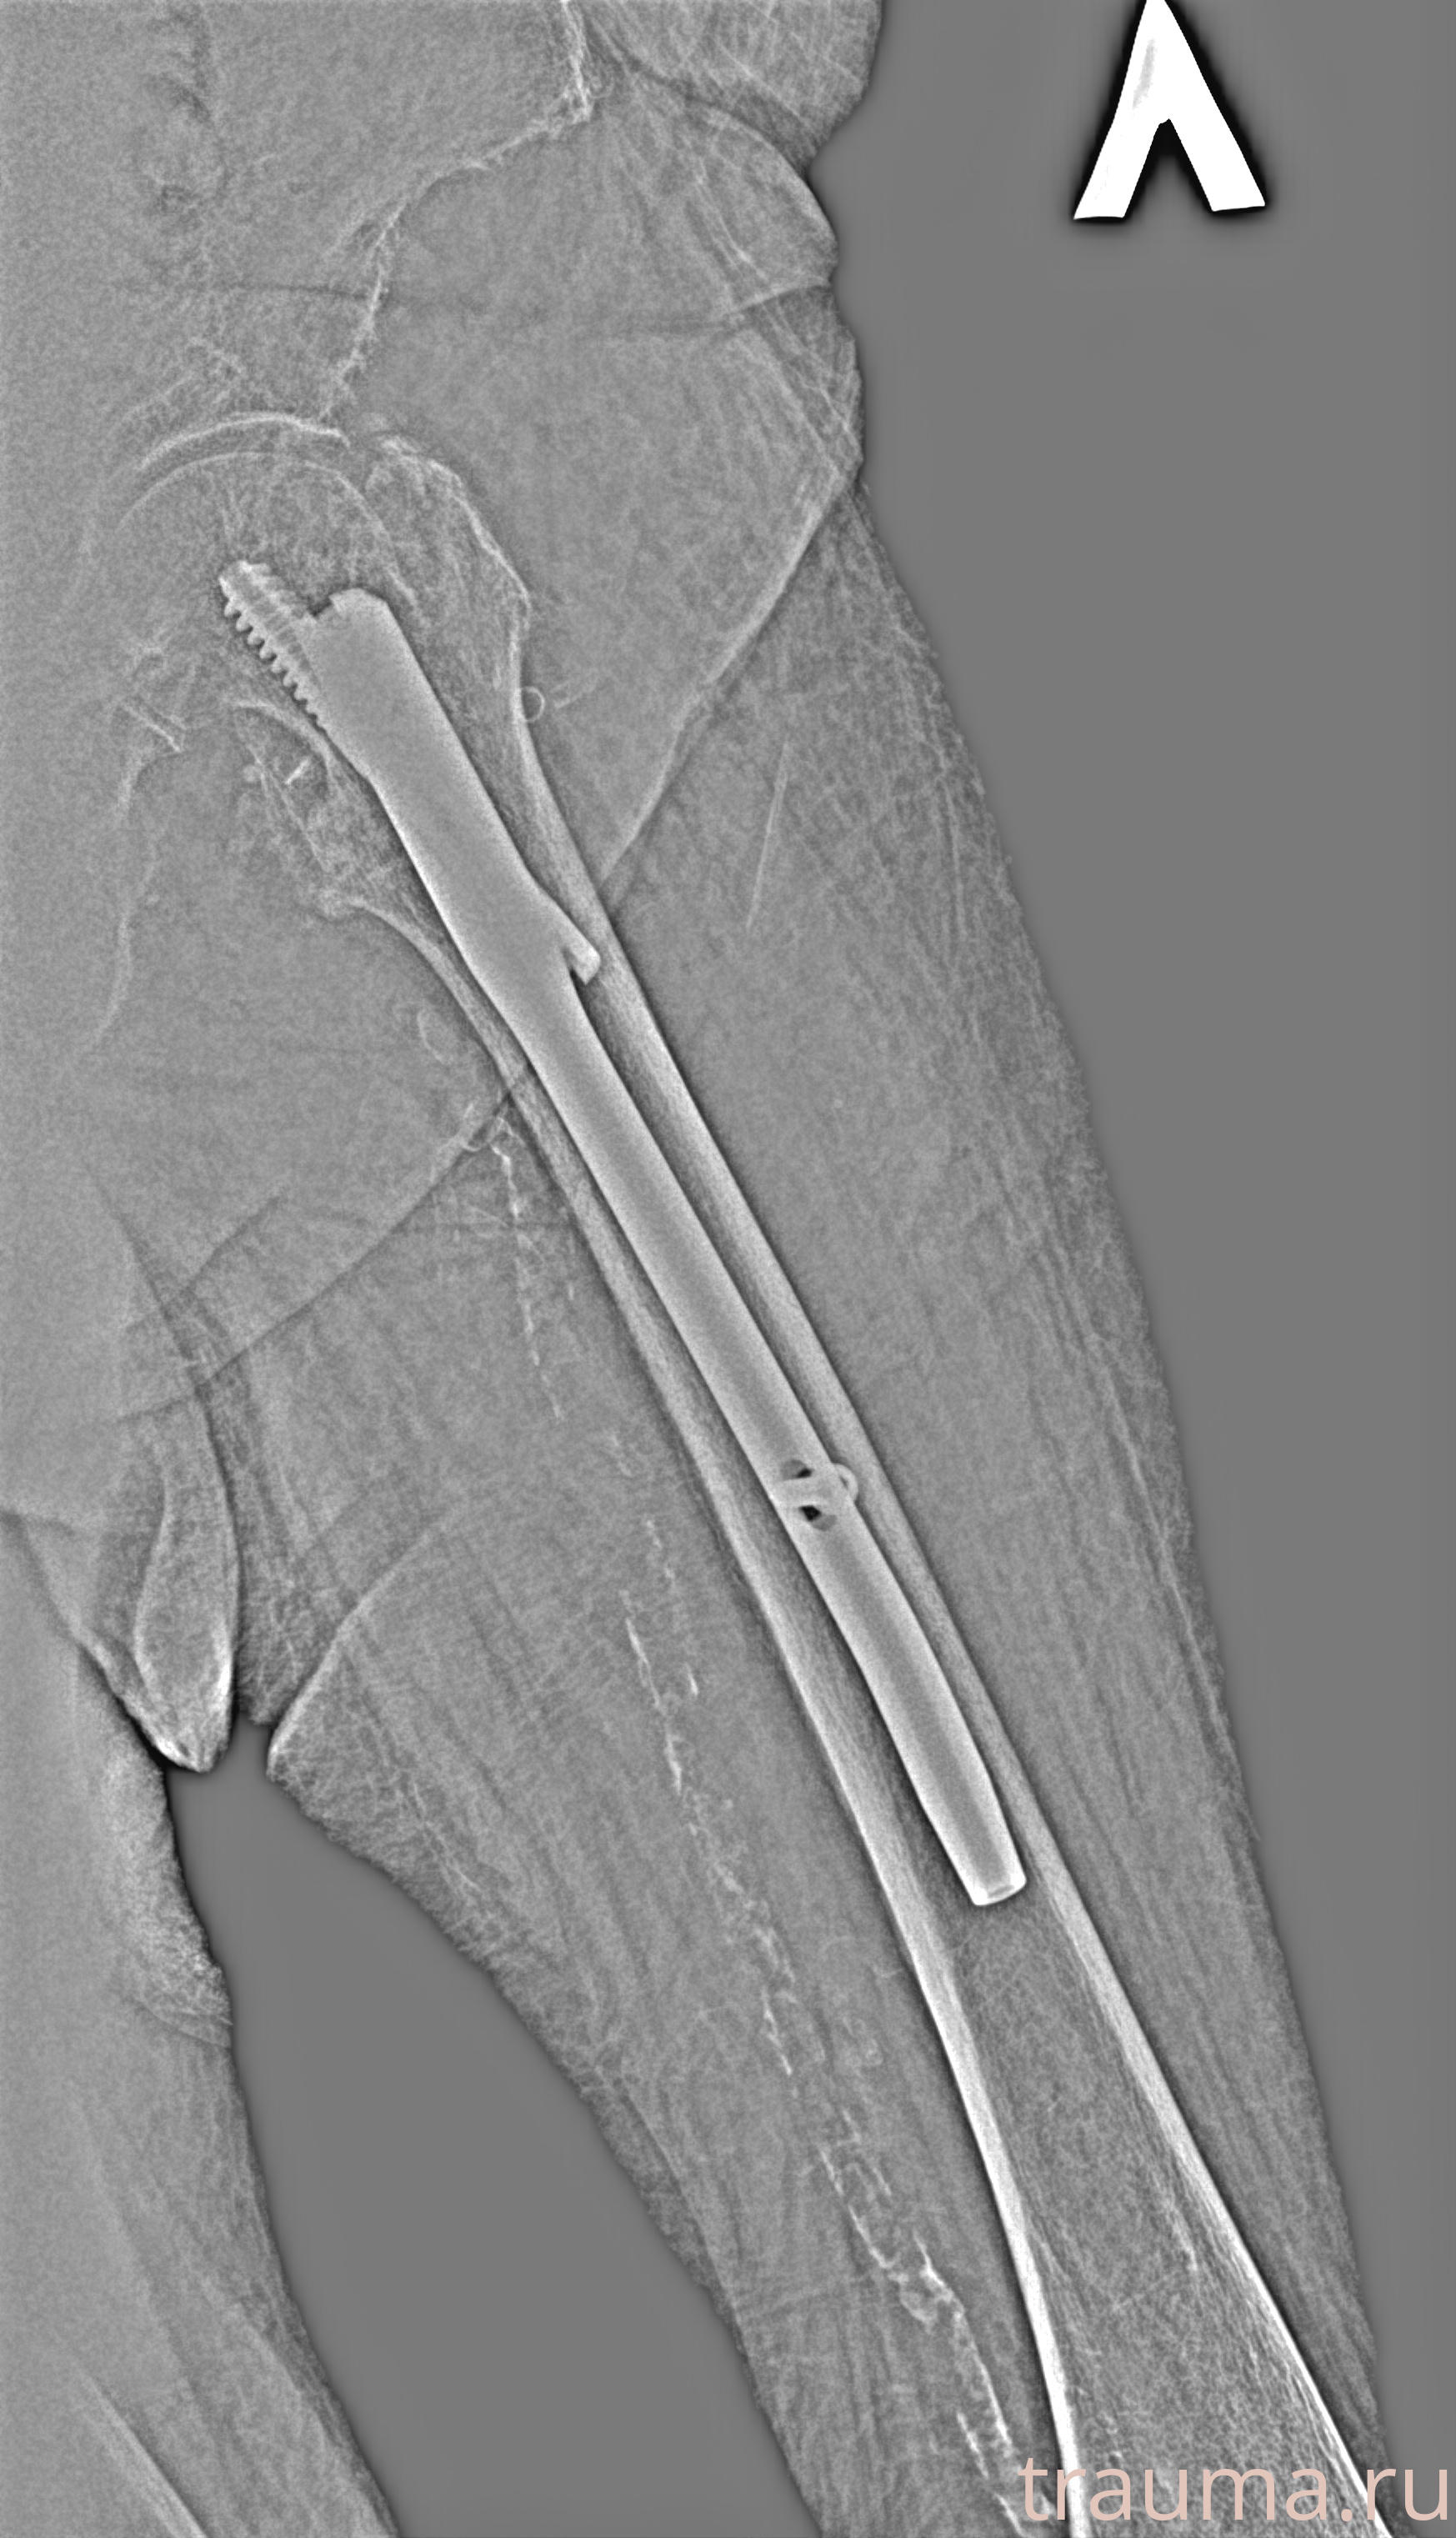

Рентгенограммы